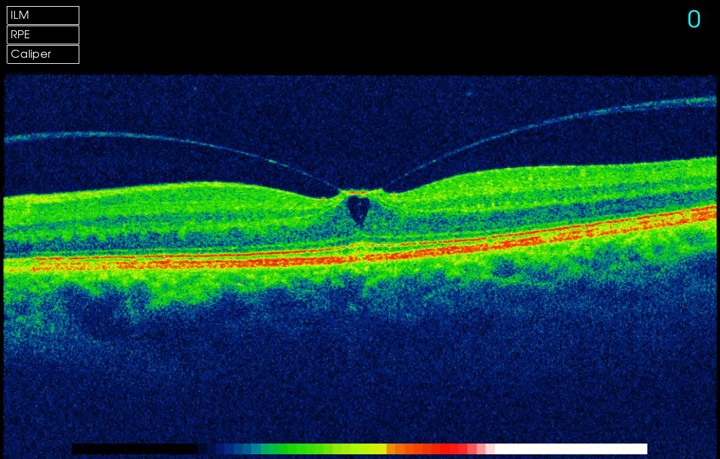

The instrument is incredibly good at measuring and monitoring Macular Degeneration.  It can measure the thickness of the optic nerves which are affected by Glaucoma (and compare to an age, gender and ethnically matched normal).

A 3D section of the layers ofthe retina and vitreous jellyA 3D section of the layers of the retina and vitreous jellyAge-related Macular Degeneration Dry FormAge-related Macular Degeneration Dry FormAge-related Macular Degeneration Wet FormAge-related Macular Degeneration Wet FormThe vitreous (jelly) pulling on the retinaThe vitreous (jelly) pulling on the retinaImage of Retina (back of the eye)Image of Retina (back of the eye)